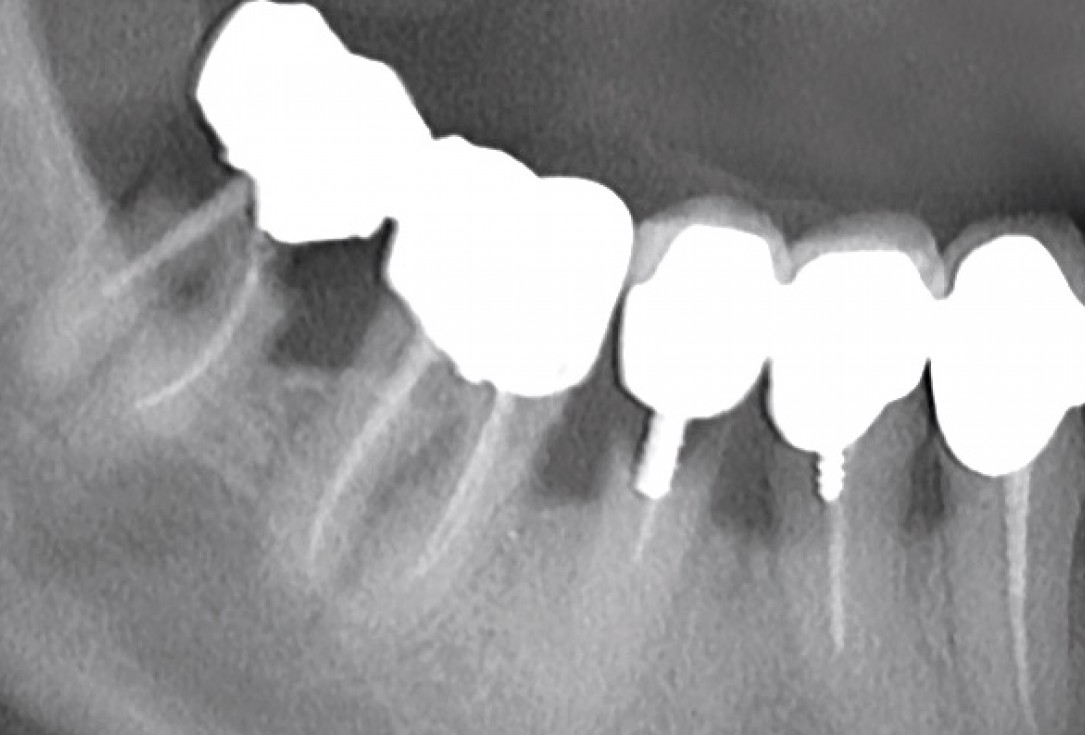

Multiple socket preservation in the mandibular with collacone® max – Dr. D. Jelušić